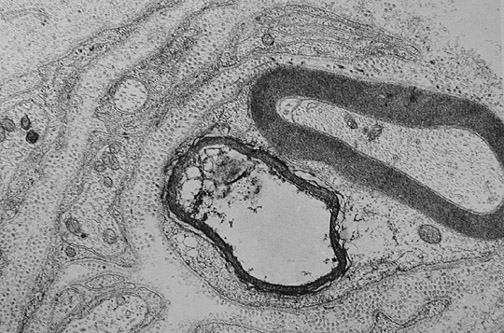

| This electron micrograph demonstrates Schwann cell basement membrane surrounding regrowing axons that have followed the nerve peripherally following injury. Whichever axon reaches the end first will win, and remains myelinated and supported by the Schwann cell. Others will degenerate. Normally, only a single axon per internode is supported by a Schwann cell in a myelinated peripheral nerve. (The dot-like structures are collagen fibers seen on end.) |